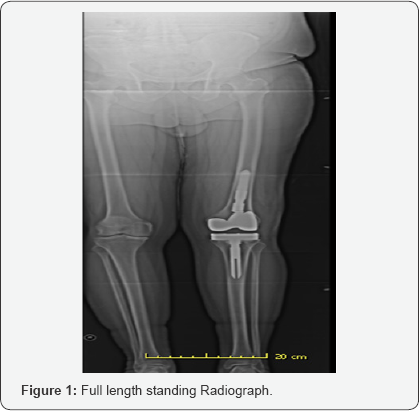

Upon physical examination, it was noted that the patient had a large joint effusion on the left knee and was slightly warm to touch when compared to contralateral knee. The incision site had healed with a supple scar and good cosmesis. Focal tenderness to palpation was noted over medial and lateral femoral condyle. Range of motion was 0-105 degrees measured with a goniometer. The patient had well balanced ligaments throughout arc of motion with appropriate patella tracking and no subsequent subluxation or dislocation. Longstanding lower extremity radiographic evaluation showed 1.3 degree valgus mechanical axis with 91.5 degree medial femoral articular angle and a 90 degree medial tibial articular angle. Radiographs including AP/ Lateral/merchant views showed overhang of lateral aspect of femoral component. Tibial component was well sized. The joint line and patella height appeared within normal limits.

The initial plan was to perform a basic infectious workup with erythrocyte sedimentation rate (ESR) and C-reactive protein (CRP). Knee arthrocentesis was performed and sent for synovial fluid cell count with differential, gram stain, culture and sensitivities, crystal analysis, alpha defensin, synovial CRP and human neutrophil elastase testing. Results revealed an ESR of 60 (normal range 0-22), and a CRP of 1.03 (<.8 normal). Cell count with differential was 606 white blood cell counts with 15% segmented neutrophils which decreased the likelihood of prosthetic joint infection. Crystal analysis was negative and final cultures showed no growth. Synovial CRP, alpha defensin and human neutrophil elastase testing were negative or within normal limits. The patient returned three weeks later with knee pain out of proportion to what would be expected for oversized or malpositioned components. ESR and CRP were again repeated with similar results. A metal allergy serum assay was ordered to rule out metal hypersensitivity. One month later, the results of the metal allergy testing did show reactivity to nickel. The patient elected to proceed with TKA revision with oxidized zirconium (Oxinium, Smith & Nephew) hypoallergenic components. (Figures 1-4) Postoperative lower extremity radiographs.

On subsequent postoperative visits, patient progressed well and was ambulating with a cane by 8 weeks. His pain was overall improved and he had an arc of motion of had 0-110 degrees of flexion. The knee was stable to varus and valgus stress. At 20 weeks postoperative, the patient continued to progress well. Passive range of motion was 0-110 degrees and full strength in quadriceps and hamstring was noted. Radiographs showed overall well sized and well positioned components.